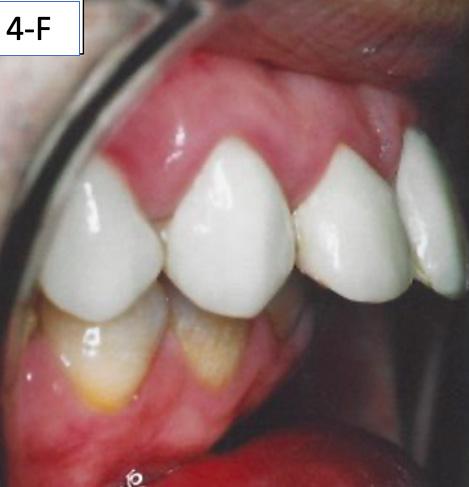

FIG. 4F: Pre-treatment, OB and OJ

Clinical dental appraisal revealed full Angle Class II molar and cuspid relationship. The arches were wide and there was a moderate crowding. The patient had 9.0 mm overjet and 6.0 mm overbite. However, the patient reported SDB symptoms, and he also presented with symptoms and signs of TM dysfunction (Figure 4A, B, C, D, E, F))

Clinical Micro-esthetic appraisal revealed signs of attrition and abrasion. Periodontal health was good, and the patient was devoid of tooth decay. However, there was a moderate number of restorations, generalized Tetracycline stain and failing porcelain veneers on the maxillary anterior teeth.